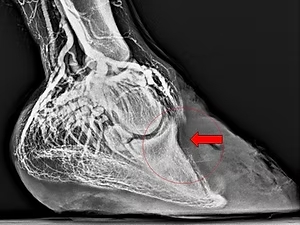

„Venographie der distalen Zehe“ von Dr. Mark Zengerling

Dr. Mark Zengerling hat am 08. November 2019 bei der Fortbildungsveranstaltung mit derbymed-Livisto in unserer Klinik diesen interessanten Vortrag gehalten.

Interessierte können diesen gerne hier nachlesen: Vortrag